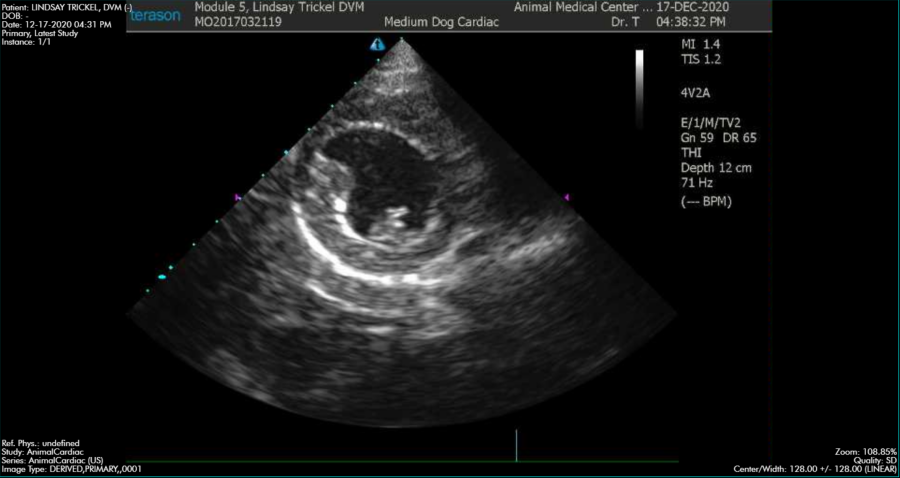

An echocardiogram is an ultrasound of the heart. It uses ultrasound waves to create images that allow the veterinarian to evaluate the heart size, valve function, and heart strength. It is considered the most accurate test for diagnosing heart disease in dogs and cats.

Echocardiography uses high-frequency sound to create an image of the heart. The machine’s small, handheld probe is placed on the pet’s chest. It delivers the sound waves through the body to the heart muscle and valves. The image created from the sound waves gives the veterinarian a view of the heart chambers, how much they contract, the valves that separate the chambers, and the vessels coming from the heart.